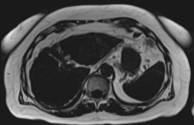

Body MR imaging — like the 3D T1 exam — can provide important clinical information but the exam itself takes time. “The 3D T1 pre- and post-contrast sequence is one of the most important sequences for body imaging,” said Bachir Taouli, M.D., professor of radiology at Mt. Sinai in New York, NY. “It’s a volumetric acquisition; we rely on it to detect and characterize cancer or lesions in the liver, kidneys, and pelvis, for example. So it’s very important for us.”

Mt. Sinai is using Caipirinha, a unique parallel imaging acquisition technique that can be used with the 3D T1 VIBE or 3D Dixon technique. CAIPIRINHA can cut breath holds for 3D T1 exams in half without impacting image resolution, coverage, or contrast. The technique is helping to reduce breath holds for Mt. Sinai’s patients.

“We used to give them 15-20 second breath holds but we’re trying to get away from that because 20 seconds is quite long. If you repeat that multiple times, it can get really challenging for older patients or patients who are frail,” said Taouli. With Caipirinha, technologists at Mt. Sinai are able to shorten the acquisition time to about 8 seconds.